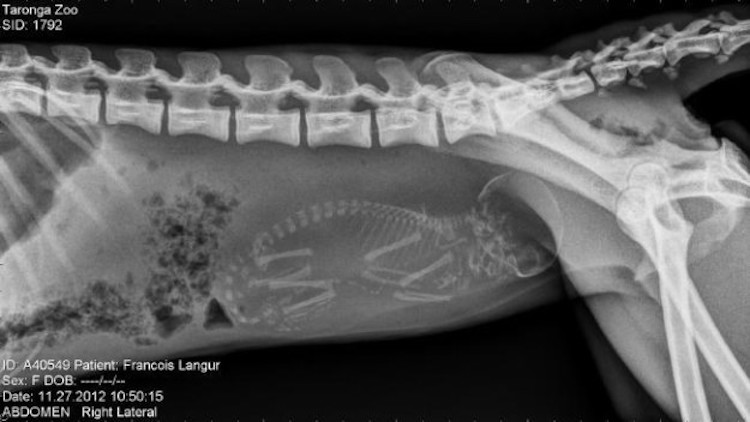

2 – Grossesse de singe (Trachypithecus francoisi). Le type d’image qui évoque évidemment les grossesses humaines.